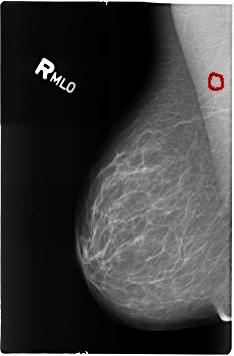

B_3165_1.RIGHT_MLO

RIGHT_MLO LINES 4624 PIXELS_PER_LINE 3032 BITS_PER_PIXEL 12 RESOLUTION 50 OVERLAY

FILE: B_3165_1.RIGHT_MLO.OVERLAY

TOTAL_ABNORMALITIES 1

ABNORMALITY 1

LESION_TYPE CALCIFICATION TYPE LUCENT_CENTER DISTRIBUTION N/A

ASSESSMENT 2

SUBTLETY 3

PATHOLOGY BENIGN_WITHOUT_CALLBACK

TOTAL_OUTLINES 1

BOUNDARY